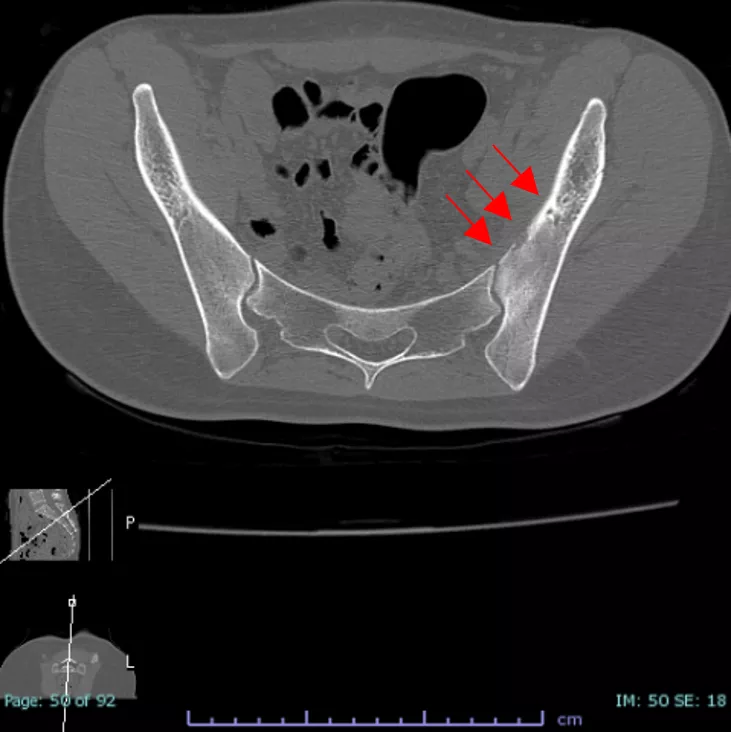

CT検査では左腸骨の骨皮質は一部欠損しており、骨びらんや骨溶解、もしくは骨折と判断できる。

CT画像所見 左腸骨の骨皮質が一部欠損している

前医にてCTはMRIと同時期に撮影していた。腸骨前方の矢印に示す骨欠損が骨折に伴うものか腫瘍による溶解像なのか、脊椎関節炎に伴う病変なのかは確定できなかった。CTガイド下生検で異常がないことを確認し、骨折の診断になった。